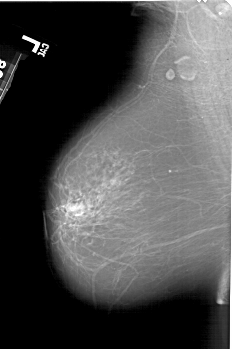

A_1539_1.LEFT_MLO

LEFT_MLO LINES 6271 PIXELS_PER_LINE 4171 BITS_PER_PIXEL 12 RESOLUTION 43.5 NON_OVERLAY